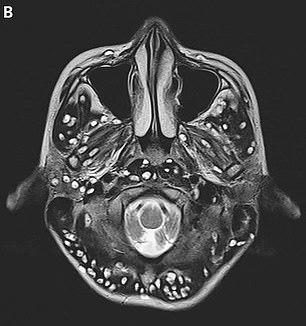

An MRI scan revealed the teen had numerous cysts in the outermost layer of his brain (cerebral cortex), which is responsible for thinking and processing information.

There were lesions in his brain stem, which is located at the base, and sends signals between the brain and the rest of the body.

Cysts were spotted in his cerebellum, located at the back of the brain responsible for coordinating voluntary movements like speech, coordination and posture.

Doctors said the extend of the damage was consisted with that of neurocysticercosis, which occurs when the parasitic larvae Taenia solium invades the body from the intestine, and builds up in the nervous system, eyes, skin and muscles.